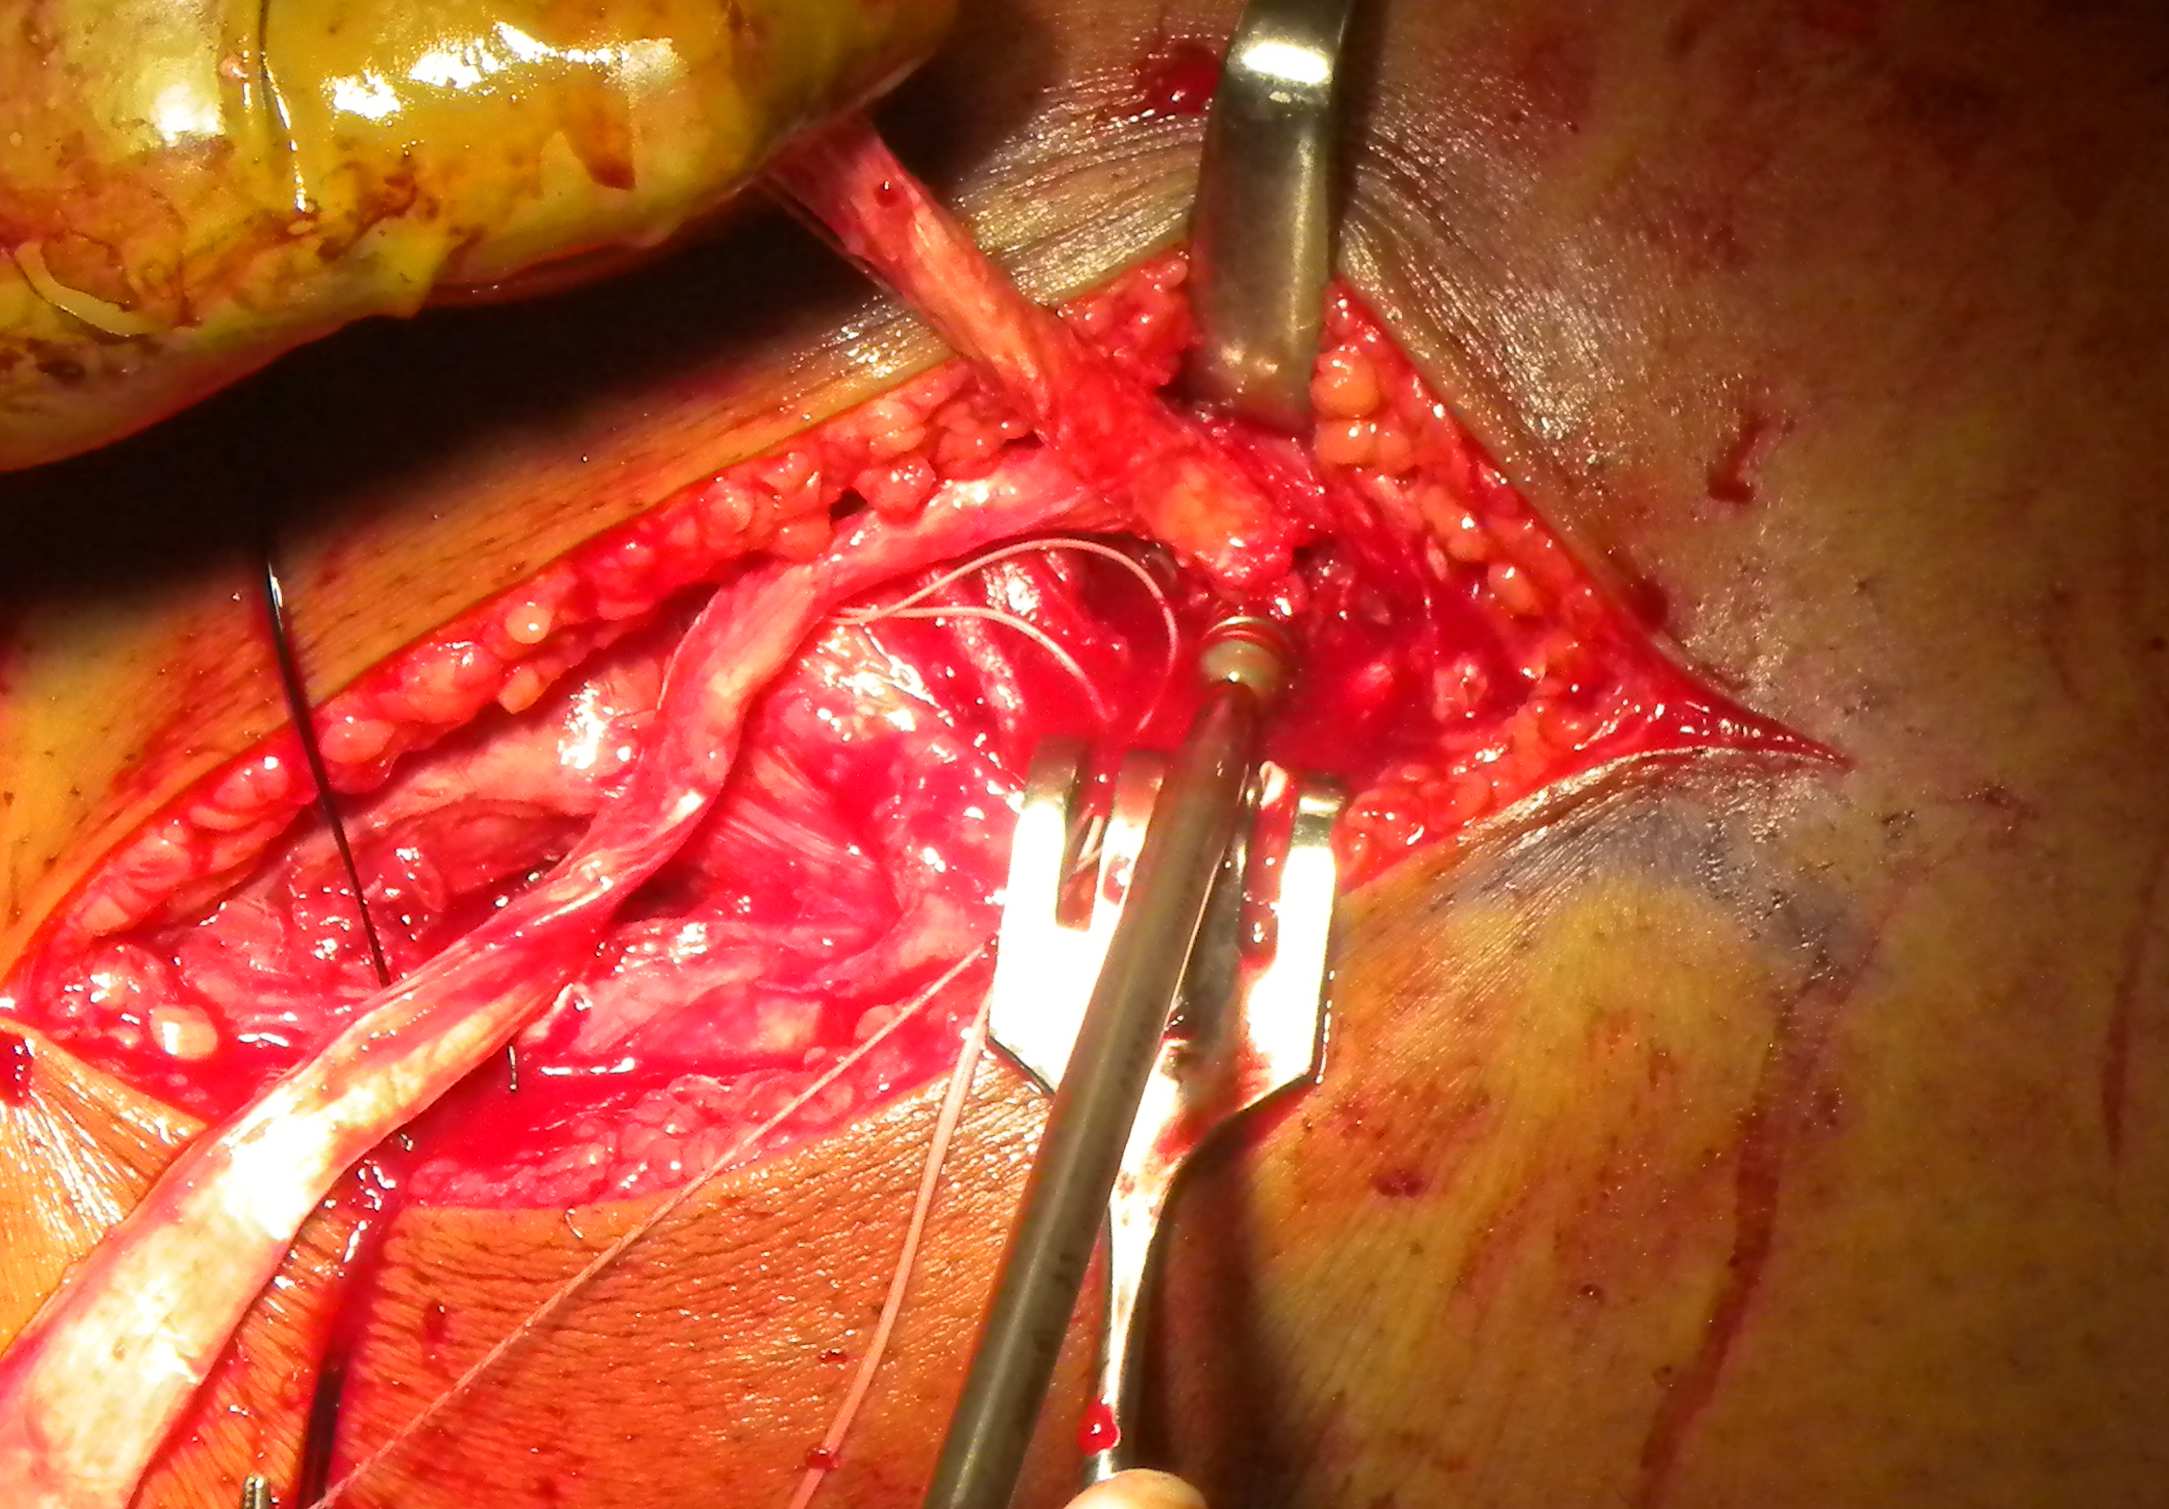

Pass popliteus tendon

- pass under IT band and the LCL

- pass back to front through tibial tunnel

PLC Popliteus Allograft Anterior Through Tibia